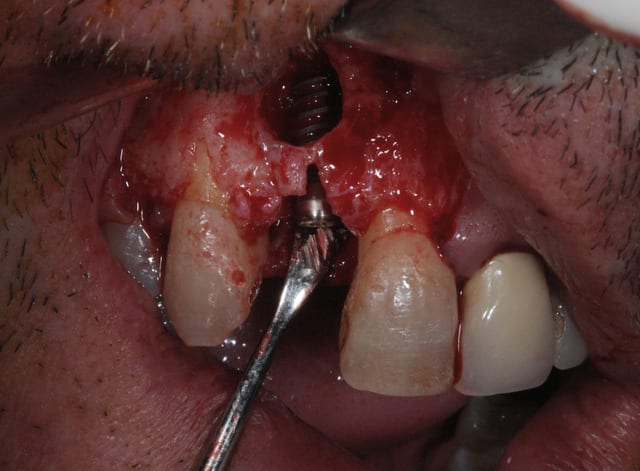

Je le mettrais plus tard sur mon book quand j'aurai fait la découverture . Je veux faire 2 publi par semaine alors je vais pas tirer toutes les cartouches tout de suite.

Je poste le cas en avant premiere ici.

C'est tout frais du mois dernier.

Le problème de faire comme ça c'est que tu positionnes ton implant au hasard. Tu fais une estimation de la position verticale de ton rebord osseux après cicatrisation.

La photo #4 montre l'implant en position finale ?

Oui, l'implant est en position finale sur la photo 4.

J'ai bien cureté. Je considère que j'ai suffisamment diminué la charge bactérienne pour éviter une infection. Je mets quand même sous antibio : ceinture et bretelles.